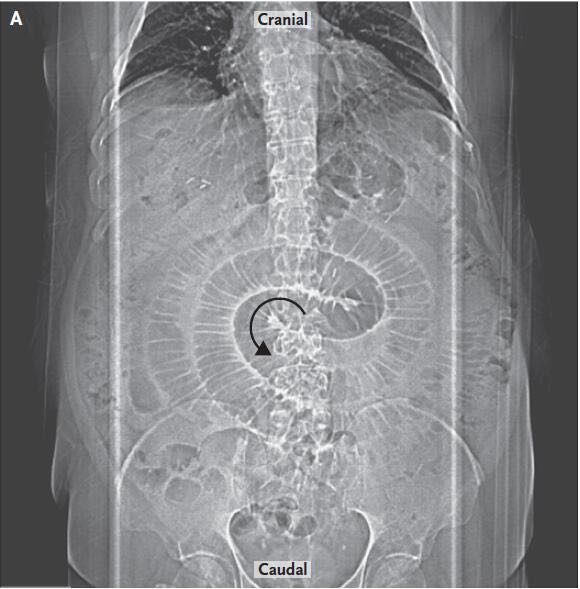

体格检查期间,该例患者心动过速、呼吸急促。 腹部检查显示腹部鼓起,膨胀,伴有严重全身性腹部压痛,反跳痛与腹膜炎表现一致。 放射X线(图A)和计算机断层扫描(CT)(图B)显示小肠呈环型扩张远端接近吻合术缝合线,近端压力降低。 通过CT可明显观察到,肠和肠系膜血管旋转,当它们穿过肠系膜空肠吻合术肠系膜缺损时形成小肠腹内疝。腹腔镜探查显示小肠腹内疝。通过处理,减小疝囊,缺损闭合。